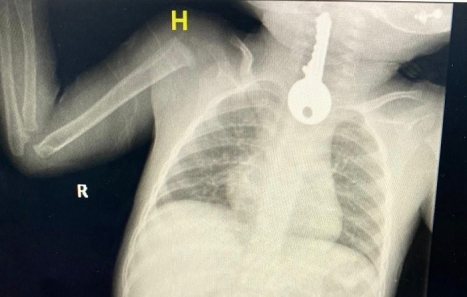

تمكن فريق طبي في محافظة الطائف السعودية من إنقاذ طفل كاد أن يفارق الحياة بعد ابتلاعه مفتاحا استقر في مريئه.

وذكرمجمع الملك فيصل الطبي عبر حسابه الرسمي على موقع التواصل الاجتماعي "تويتر"بأنهم استقبلوا حالة طفل في وضع صحي حرج، حيث كان يعاني من ضيق في التنفس مما استدعى تقديم الإسعافات الأولية وإجراء الفحوصات السريرية والشعاعية.

وأوضح المجمع أن الصور الشعاعية كشفت وجود مفتاح في المريء.

وأوضح الفريق المعالج للحالة أنه تم على الفور عمل منظار عاجل واستخراج المفتاح الحديدي من مريء الطفل الذي كاد أن يودي بحياته.